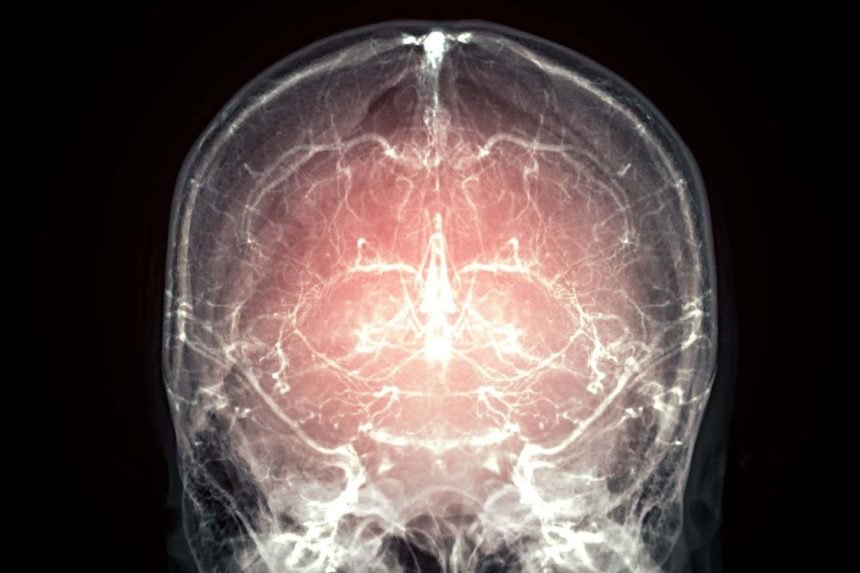

Could our brains one day be preserved in a way that locks in our thoughts, feelings and perceptions?

A full mammalian brain has been successfully preserved using a new technique that will soon be available to terminally ill individuals. The goal is to preserve essential neural information for potentially reconstructing the person’s mind in the future.

Wróbel suggests that, in theory, this protocol could be used to reconstruct the three-dimensional structure of neurons and their connections, known as the connectome. By mapping the connectome, it might be possible to gain insights into how the brain produces thoughts, feelings, and perceptions. To date, only a small portion of the mouse brain has been mapped in this way, a process that took seven years to complete.